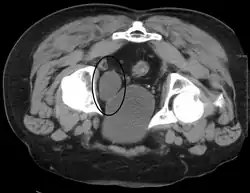

Investigations performed usually include collecting a sample of urine for an inspection for malignant cells under a microscope, called cytology, as well as medical imaging by a CT urogram or ultrasound.[33] If a concerning lesion is seen, a flexible camera may be inserted into the bladder, called cystoscopy, in order to view the lesion and take a biopsy, and a CT scan will be performed of other body parts (a CT scan of the chest, abdomen and pelvis) to look for additional metastatic lesions.[33]

Some forms of medical imaging exist to visualise the bladder. A bladder ultrasound may be conducted to view how much urine is within the bladder, indicating urinary retention. A urinary tract ultrasound, conducted by a more trained operator, may be conducted to view whether there are stones, tumours or sites of obstruction within the bladder and urinary tract. A CT scan may also be ordered.